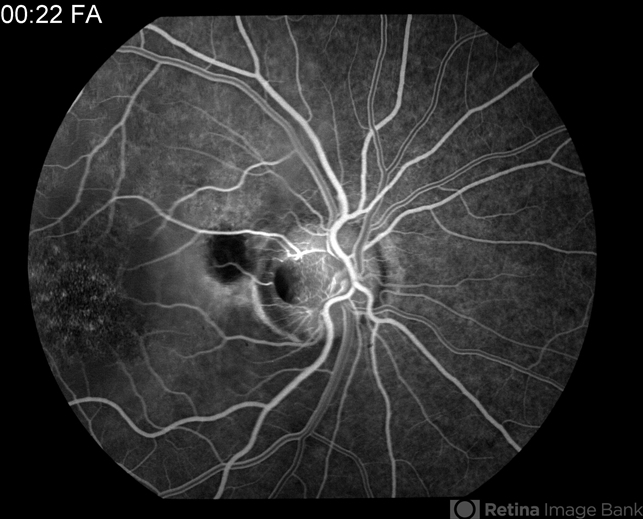

By Raj K. Maturi, MD

Midwest Eye Institute & Retina Partners Midwest - Uploaded on Aug 30, 2012.

- optic nerve pit

- Tom Steele, CRA, Midwest Eye Institute

Fundus camera

Topcon Ex